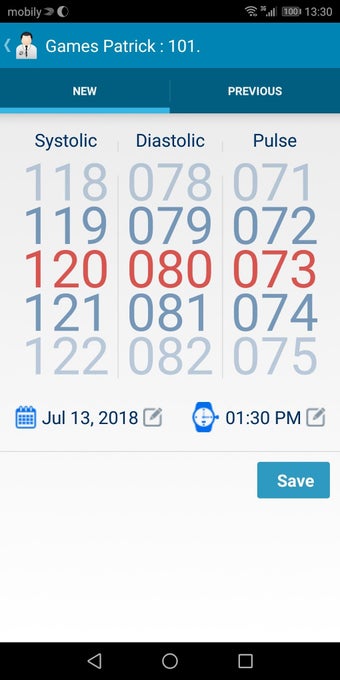

In addition, the app has a blood pressure module that measures systolic, diastolic, and pulse, and allows users to export blood pressure reports to either PDF or graphs. The app also has a blood glucose (sugar) module that records blood sugar values and allows users to export blood glucose reports to either PDF or graphs. Users can also send blood pressure and blood sugar reports to their doctor. The app is compatible with multiple screens, including phones and tablets, and works on Chromebook systems. Overall, the Android Medical Records App is a great tool for patients and physicians alike for managing patient information and medical records.